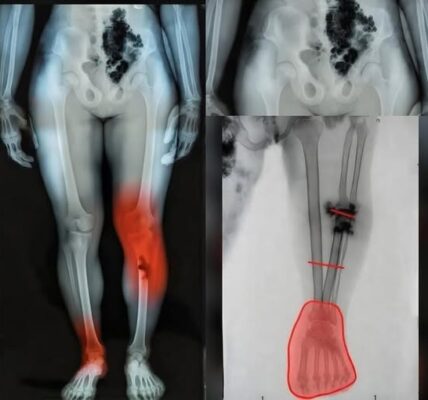

Wichtiges Warnzeichen für Krebs, das man nur nachts erkennen kann

Krebs ist eine verheerende Krankheit, und im Jahr 2025 werden in den Vereinigten Staaten unglaubliche 618.120 Menschen daran sterben. Wir alle kennen jemanden, der betroffen ist – deshalb sind Aufklärung und Früherkennung so wichtig. Erschreckenderweise überlebt nur die Hälfte aller…